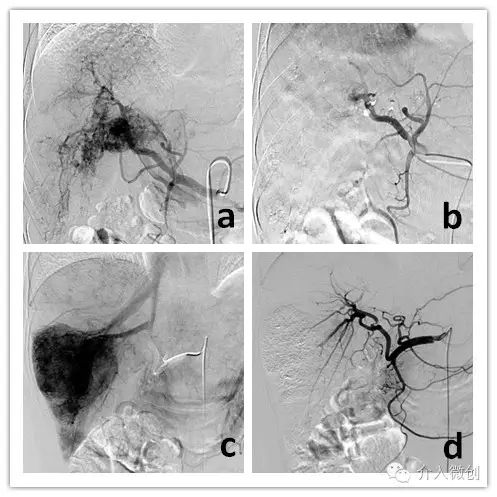

肝动脉化疗栓塞+经皮瘤内注药联合控制肝脏肿瘤